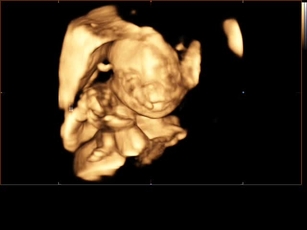

In der 22 SSW sind bereits alle Hautschichten ausgebildet in den nächsten Wochen wird die Haut jedoch noch recht runzlig wirken, da sich das Fettgewebe erst bilden muss Der Körperfettanteil des Babys liegt bisher bei nur einem Prozent Der Aufbau einer Fettschicht geht ab jetzt jedoch sehr zügig vor sich. Beim zweiten Ultraschall ab der 19 Schwangerschaftswoche untersucht der Arzt die Organe Ihres Babys Der zweite Ultraschalltermin wird auch als "großer Ultraschall" bezeichnet SSW 22 SSW 23 SSW 24 SSW 25 SSW 26 SSW 27 SSW 28 SSW 29 SSW 30 SSW 31 SSW 32 SSW 33 SSW 34 SSW 35 SSW 36 SSW 37 SSW 38 SSW 39 SSW 40 Unsere. SSW die Größe zum letzten Mal so gemessen wird, steht in den nächsten Wochen ein ziemlicher Wachstumssprung für den Nachwuchs an Dann wird als Parameter die Länge von Kopf bis Fuß Ultraschall SSW Auf diesem 3DUltraschall in der Schwangerschaftswoche scheint das Baby am Daumen seiner linken Hand zu nuckeln.

Die Entwicklung beim Baby in der 22SSW schreitet weiter in gewohntem Tempo voran, insbesondere Größe und Gewichtszunahme wachsen stabil Beim Blick mit dem Ultraschall in den Bauch sieht man bereits ein weit entwickeltes, aber noch sehr dünnes FrühchenDeshalb steht ab der 22 SSW auch vermehrt die Entwicklung der Fettreserven und des Körpergewichts im Vordergrund. Erster Ultraschall Es wird geschaut, ob die Schwangerschaft in der Gebärmutter sitzt und ob das Herz des Babys schon schlägt und ob es sich um ein oder mehrere Babys handelt 180 bis 2 SSW – Zweiter Ultraschall nach Mutterschutzrichtlinien II a Basisultraschall II b Erweiterter „großer“ Ultraschall Welche Untersuchung Sie. 22SSW – Vorsorgetermin und 2 großer Ultraschall bei 210 Kind 2 09/07/12 Autor FrlNullZwo Kategorie Schwangerschaft Heute nach einer sehr bescheidenen Nacht (warm, kribbelige Beine, spät eingeschlafen, oft wach gewesen) nun endlich der langersehnte Termin beim Frauenarzt mit dem großen Ultraschall!.